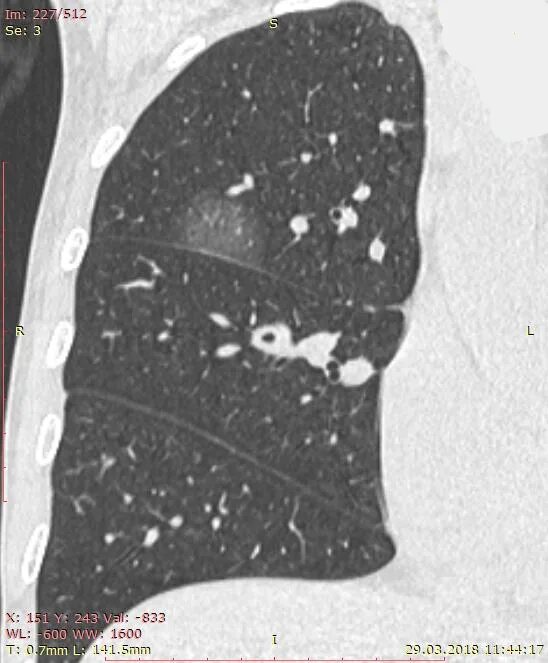

Уплотнения паренхимы по типу матового стекла